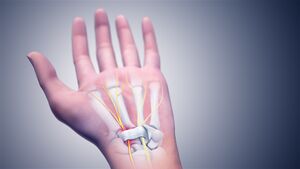

In the human body, the carpal tunnel or carpal canal is the passageway on the palmar side of the wrist that connects the forearm to the hand.[1]

The tunnel is bounded by the bones of the wrist and flexor retinaculum from connective tissue. Normally several tendons from the flexor group of forearm muscles and the median nerve pass through it. There are described cases of variable median artery occurrence.

Structure

The carpal bones that make up the wrist form an arch which is convex on the dorsal side of the hand and concave on the palmar side. The groove on the palmar side, the sulcus carpi, is covered by the flexor retinaculum, a sheath of tough connective tissue, thus forming the carpal tunnel. On the side of the radius, the flexor retinaculum is attached to the scaphoid bone, more precisely its tubercle, as well as the ridge of trapezium. On the ulnar side, it is attached to the pisiform and hook of hamate.[4]

The narrowest section of the tunnel is located a centimetre beyond the mid-line of the distal row of carpal bones where the sectional area is limited to 1.6 cm2.[2]